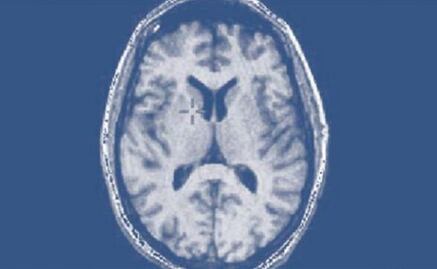

Los investigadores han descubierto ahora que el llamado "inhibidor tisular de la metaloproteinasa 2" ("TIMP2", sus siglas en inglés) provoca un efecto similar en el hipocampo del cerebro de ratones viejos, al tiempo que mejora sus funciones cognitivas.

Este factor de transmisión sanguínea, "enriquecido en plasma umbilical humano, plasma de ratones jóvenes y en el hipocampo de ratones jóvenes, aparece en el cebrero después de su administración sistemática en ratones viejos", destacan.

Toda vez que alcanza su objetivo, señalan, la proteína mejora la "plasticidad sináptica" y las funciones cognitivas que dependen de la actividad del hipocampo.

Los test efectuados con este tratamiento constataron que los ratones viejos experimentaron avances en su capacidad de aprendizaje, mejoraron su memoria y aumentaron la plasticidad sináptica, clave para que el cebrero procese y se adapte a nuevas informaciones.